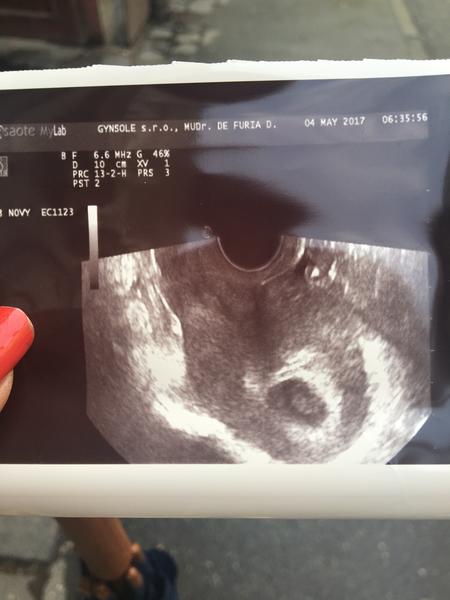

karmela

@luta13 @miriamn76 @happymia @sofija18 @nikuskaniky @barboravalikova dúfam že som neskomolila nicky a ostatne babulky moje zlate srdiečko nám krásne bije aj sme podrastli všetko je v poriadku a verím že a bude sme v 7tt som veľmi happy 😍

@karmela doktor/ka sa vola De Furia? 😂